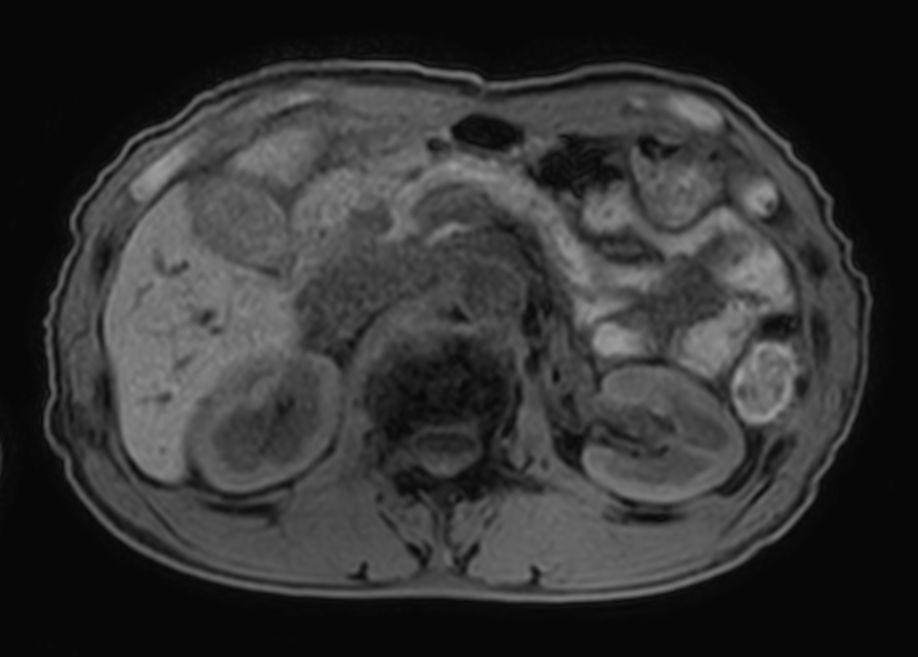

T1w FFE mDIXON XD- Compressed SENSE